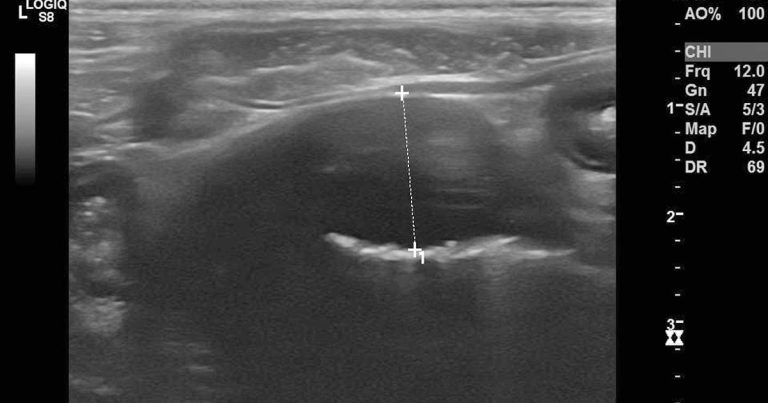

Figure 3. Ultrasound image showing the intestinal mass lesion.

Ross had surgery to excise the intestinal mass and had an uneventful recovery. Histopathology revealed alimentary lymphoma.

In this case, the AVB reported by the referring vet was, most likely, caused by an increased vagal tone due to the intestinal mass.